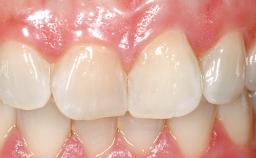

A 42-year-old female patient was referred to our clinic at the School of Dentistry of the University of São Paulo in November 2004, presenting a deficient restoration in the upper left central incisor. The clinical examination revealed no gingival retraction or any signs of gingival inflammation and, therefore, previous periodontal treatment was not considered. The patient presented a high lip line at full smile and a thin tissue biotype. This combination characterized a high-risk situation from an anatomic point of view, which required careful preoperative planning and cautious surgical execution.

Soft Tissue Contour and Volume Ideal